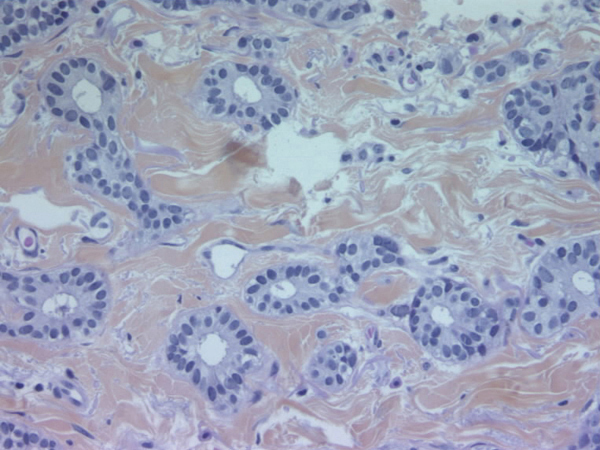

Tumeurs du sein - Tumeur exprimant fortement les récepteurs aux estrogènes

© Frédérique Penault-Llorca - La Revue du Praticien

Marquage nucléaire.